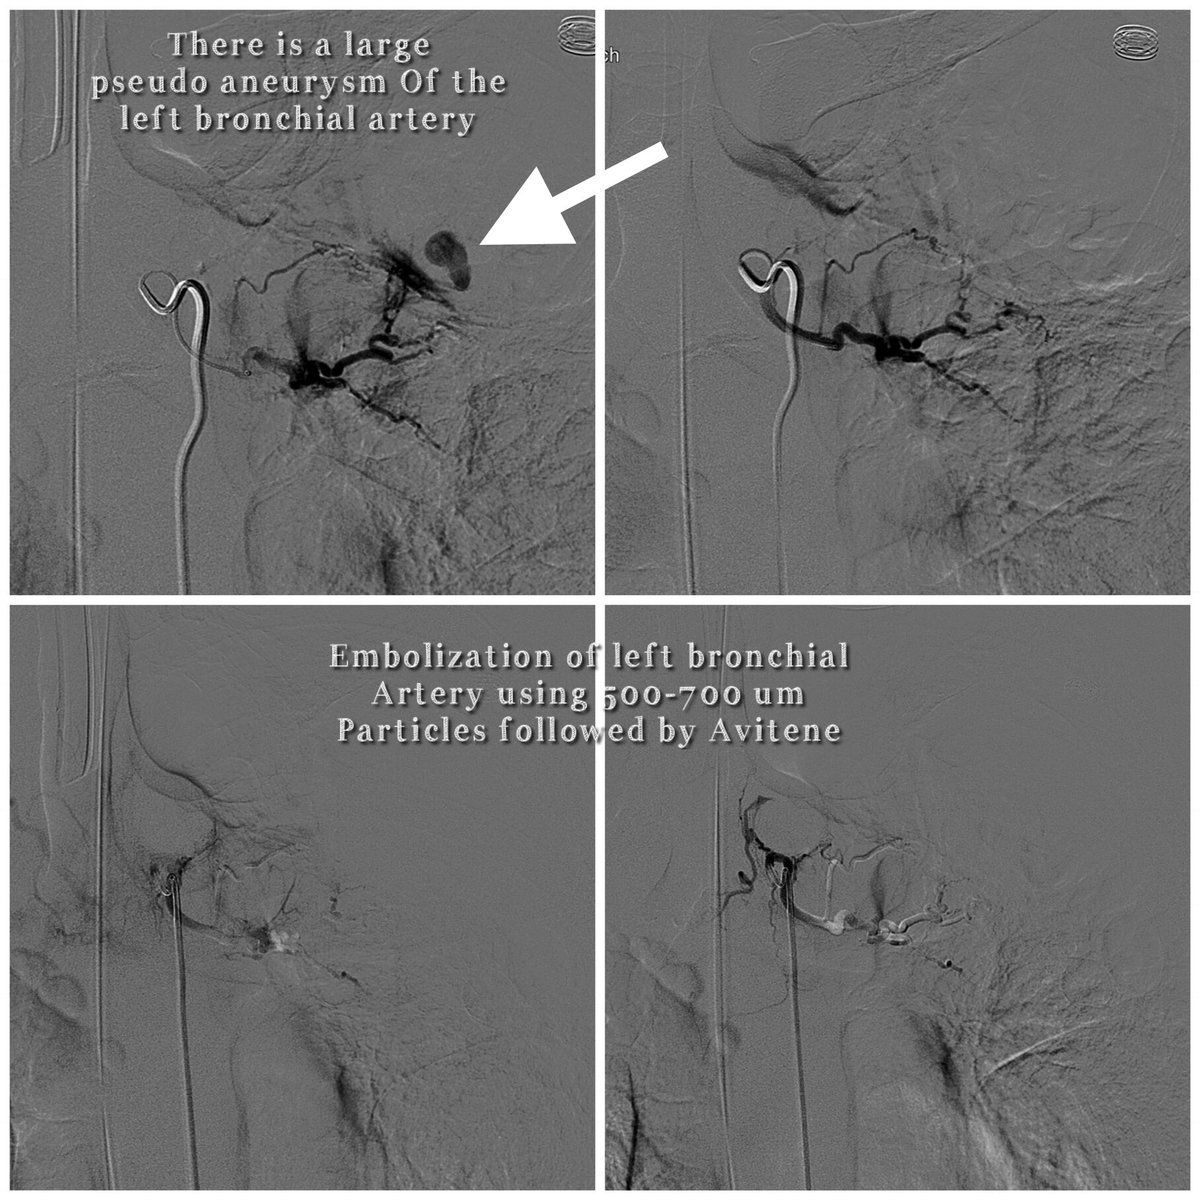

Treatment of hemoptysis by

#irads is one of the#ValueAdded to#PatientManagement and provides extra#armamentarium to other#ClinicalServices@uab_ir@uabmedicine @_BenRoush@DrAlHarbiA_Aziz@kmadass@kristenwelchh@SDhandMD@AlexCVIR@amdevane@The_Sound_of_IR@CancerGeekpic.twitter.com/Rf5t2ZYfgL